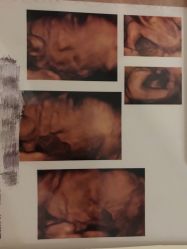

• -郑州万安妇产医院

相册

Miss_Gao 上传于 19-01-08 | 报错

婉婉777 上传于 18-12-31 | 报错